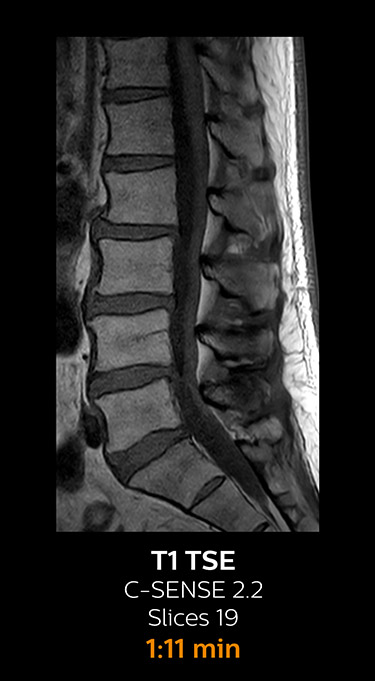

which corresponds to 34% reduction.

With Compressed SENSE, the scan time for the routine lumbar spine examination at KNC was reduced from 11:41 to 8:17 minutes,

MRI examination of the lumbar spine with Compressed SENSE

Ingenia 3.0T CX

Scan time 8:17 min. (was 11:41 min. without Compressed SENSE)